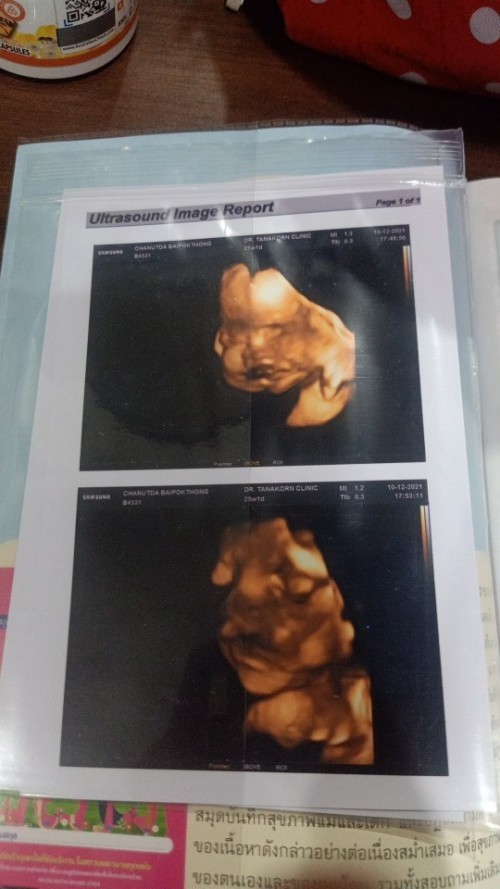

ซาวด์4มิติ ตอนนั้นอายุ25w1d ปัจจุบัน 27w4d ได้ลูกสาวค่ะดิ้นเก่งมากก😊